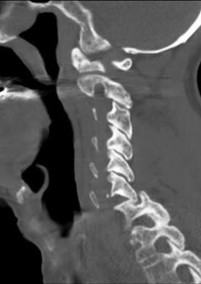

An 82-year-old male with severe chronic obstructive pulmonary disease and heart failure presents after a mechanical fall from a standing height. He reports significant neck pain. Neurologic examination is unremarkable.

Imaging demonstrates a displaced Type II odontoid fracture. What is the most appropriate management for this patient?

Explanation

A 75-year-old male sustains a Type II odontoid fracture after a ground-level fall. Which of the following radiographic factors is MOST strongly associated with non-union if treated non-operatively in a halo vest?

An 80-year-old female sustains a Type II odontoid fracture after a ground-level fall. Her family prefers conservative management over surgery due to her severe cardiac comorbidities. Which of the following is the strongest risk factor for non-union of a Type II odontoid fracture treated with a rigid cervical collar?